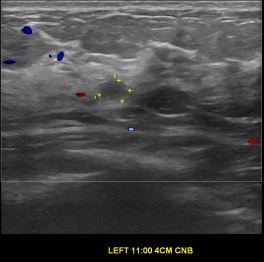

상기환자는 양성추정혹 경과관찰 하시는  50대 초반 여성분으로 의심스러운 좌측유방혹

조직검사 시행해 침윤성 유방암으로 진단되었습니다